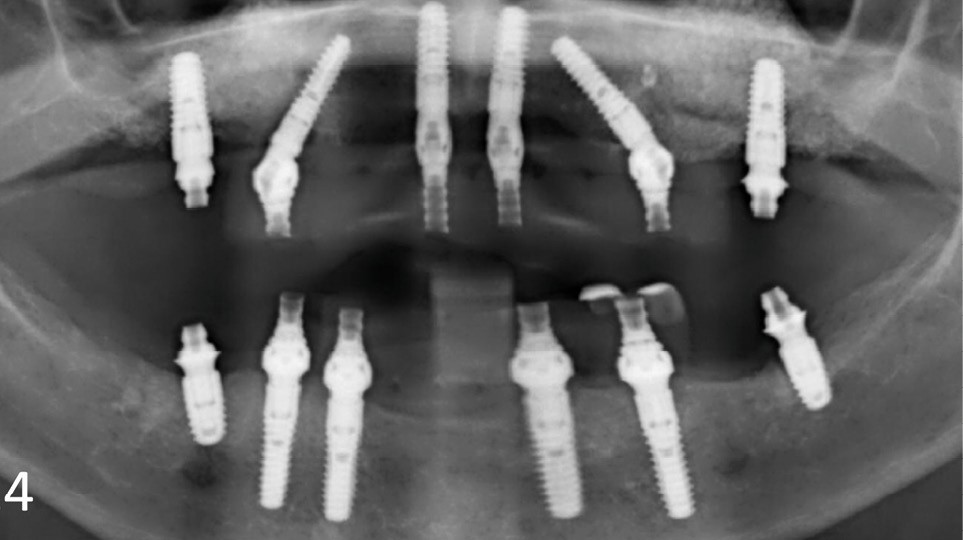

Une patiente ayant perdu ses incisives maxillaires à la suite d’un traumatisme quelques années auparavant, consulte en 2015 pour un inconfort occlusal persistant. Elle a été traitée par diverses gouttières occlusales, sans résultat notable. En 2017, une reconstruction globale est réalisée, toujours sans résolution de la plainte d’inconfort occlusal. Après avoir consulté de très nombreux praticiens et bénéficié de multiples traitements, en 2024 la patiente a perdu l’ensemble de ses dents ! En octobre 2025, après plusieurs prothèses globales sur implants, la plainte est toujours la même dans un contexte psycho-émotionnel de plus en plus difficile (fig. 1).